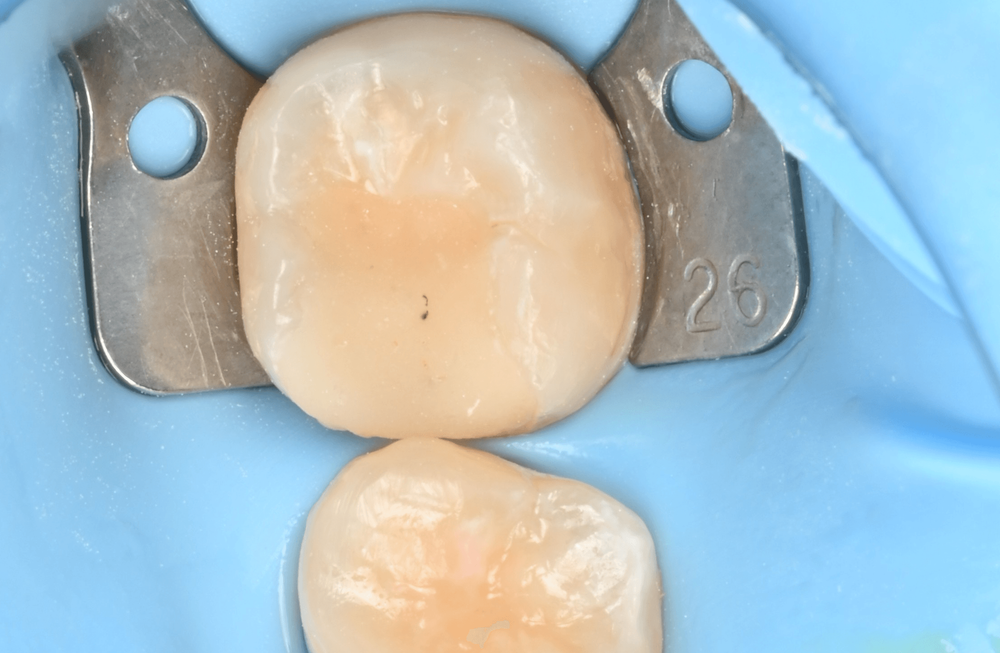

Затем мы напечатали на 3Д принтере шаблон зуба 2.8 для использования его во время операции для подготовки лунки 3.6.

После подготовки мы пересадили зуб мудрости и зафиксировали его тонкой шиной.

Через 20 дней шину сняли — зуб хорошо прижился. Спустя два месяца он уже полноценно участвовал в жевании, а снимки показывали стабильную и правильную адаптацию.